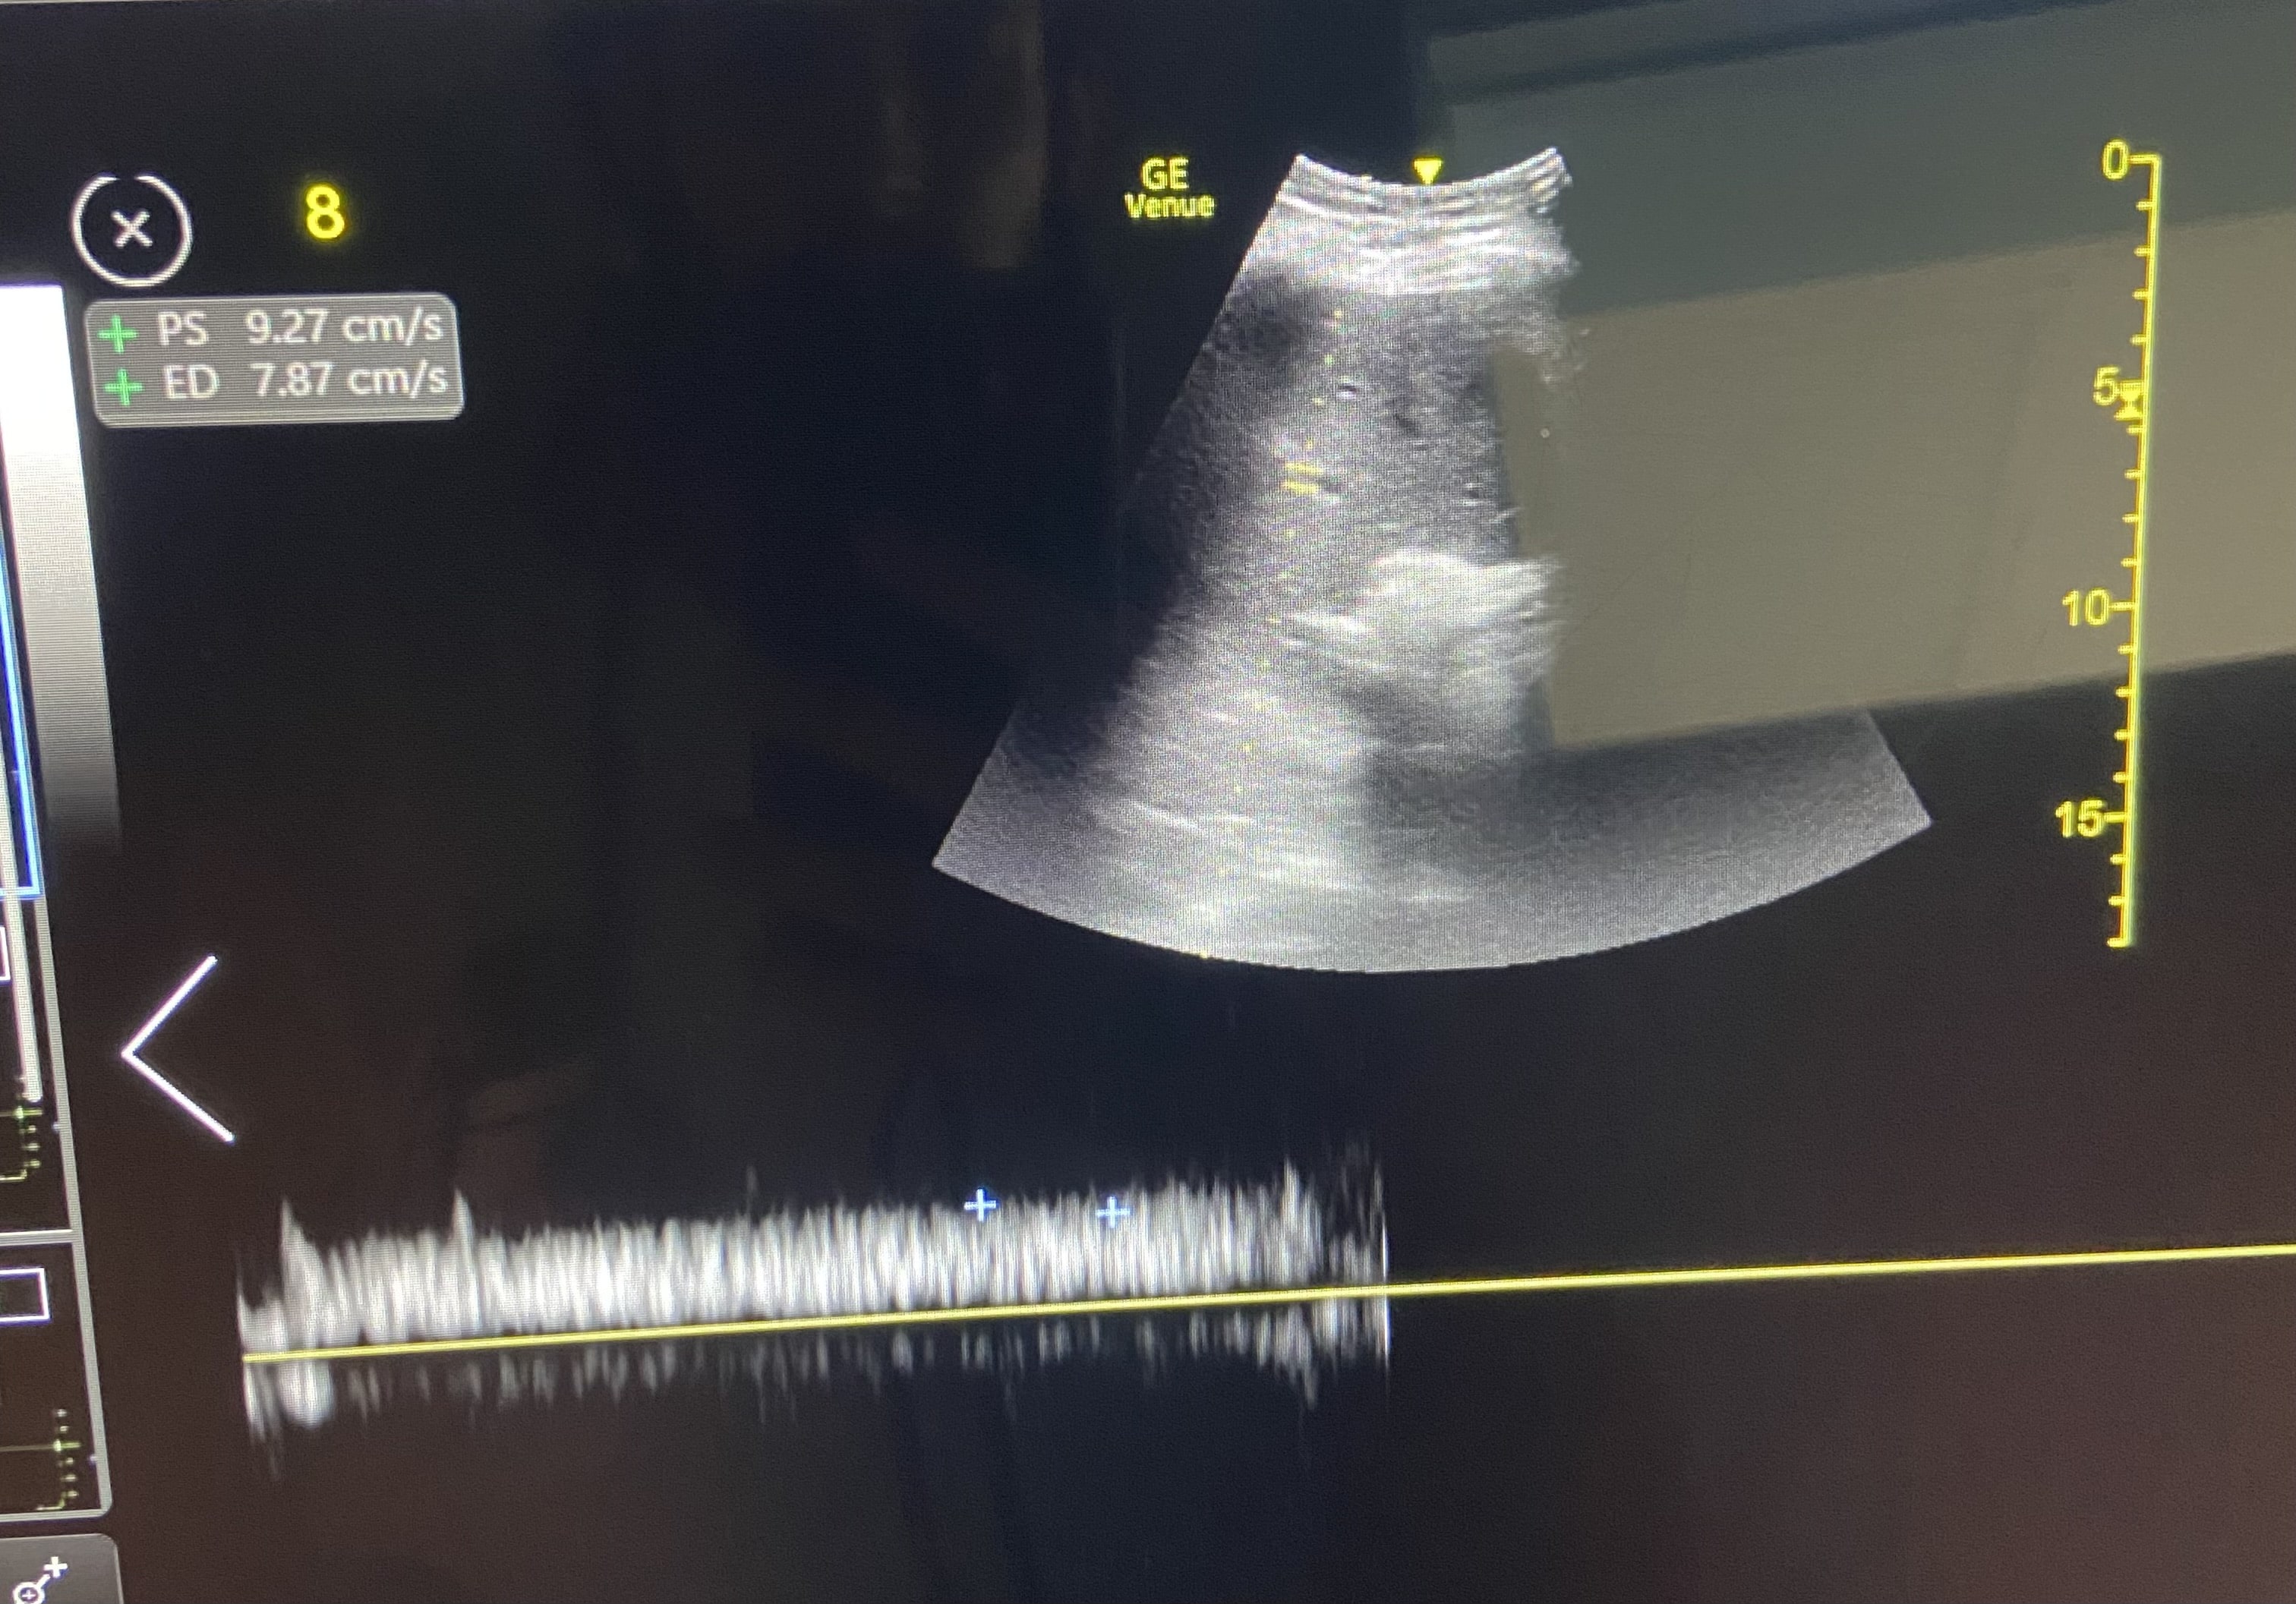

Paciente hombre de 85 años con antecedentes de insuficiencia cardiaca. Acude a urgencias por disnea progresiva de 48 horas de evolución, precedida por 10 días de ingesta deficiente. En la exploración física, presenta crepitantes bibasales hasta campos medios, edemas hasta rodillas, mucosas secas y signo del pliegue positivo. La tensión arterial es de 107/65 mmHg. Los análisis sanguíneos revelaron una creatinina de 1.8 mg/dL y un NT-proBNP de 5500 pg/mL, con una fracción de excreción de urea de 32%, compatible con origen prerrenal. Ante la aparente contradicción, se realiza una ecografía PoCUS dirigida. La vena cava inferior mostró un diámetro máximo de 2,13 cm con colapsabilidad en inspiración, y el Doppler de venas suprahepáticas, venas porta e intrarrenales no evidenció signos de congestión. En conjunto, los hallazgos configuraron un perfil VExUS Grado 1.

Se diagnostica un síndrome cardiorrenal tipo 1. El diagnóstico diferencial se establece entre una otros tipos de síndrome cardiorrenal. La ecografía orientó a una congestión vascular como principal problema a resolver en este caso complejo.

En base al perfil VExUS Grado 1 se inició tratamiento con diuréticos a dosis moderadas para tratar el componente congestivo, sin empeorar el renal.

El paciente mostró una evolución favorable con tratamiento diurético inicial. Una vez hospitalizado, el protocolo VExUS mostró un perfil con menor congestión, por lo que se pudo iniciar fluidoterapia, logrando una normalización de los parámetros renales.

Este caso demuestra que el protocolo VExUS es una herramienta dinámica, esencial para el médico de urgencias en el manejo complejo de la volemia en pacientes cardiorrenales, permitiendo una toma de decisiones segura y eficaz en situaciones clínicas complejas.